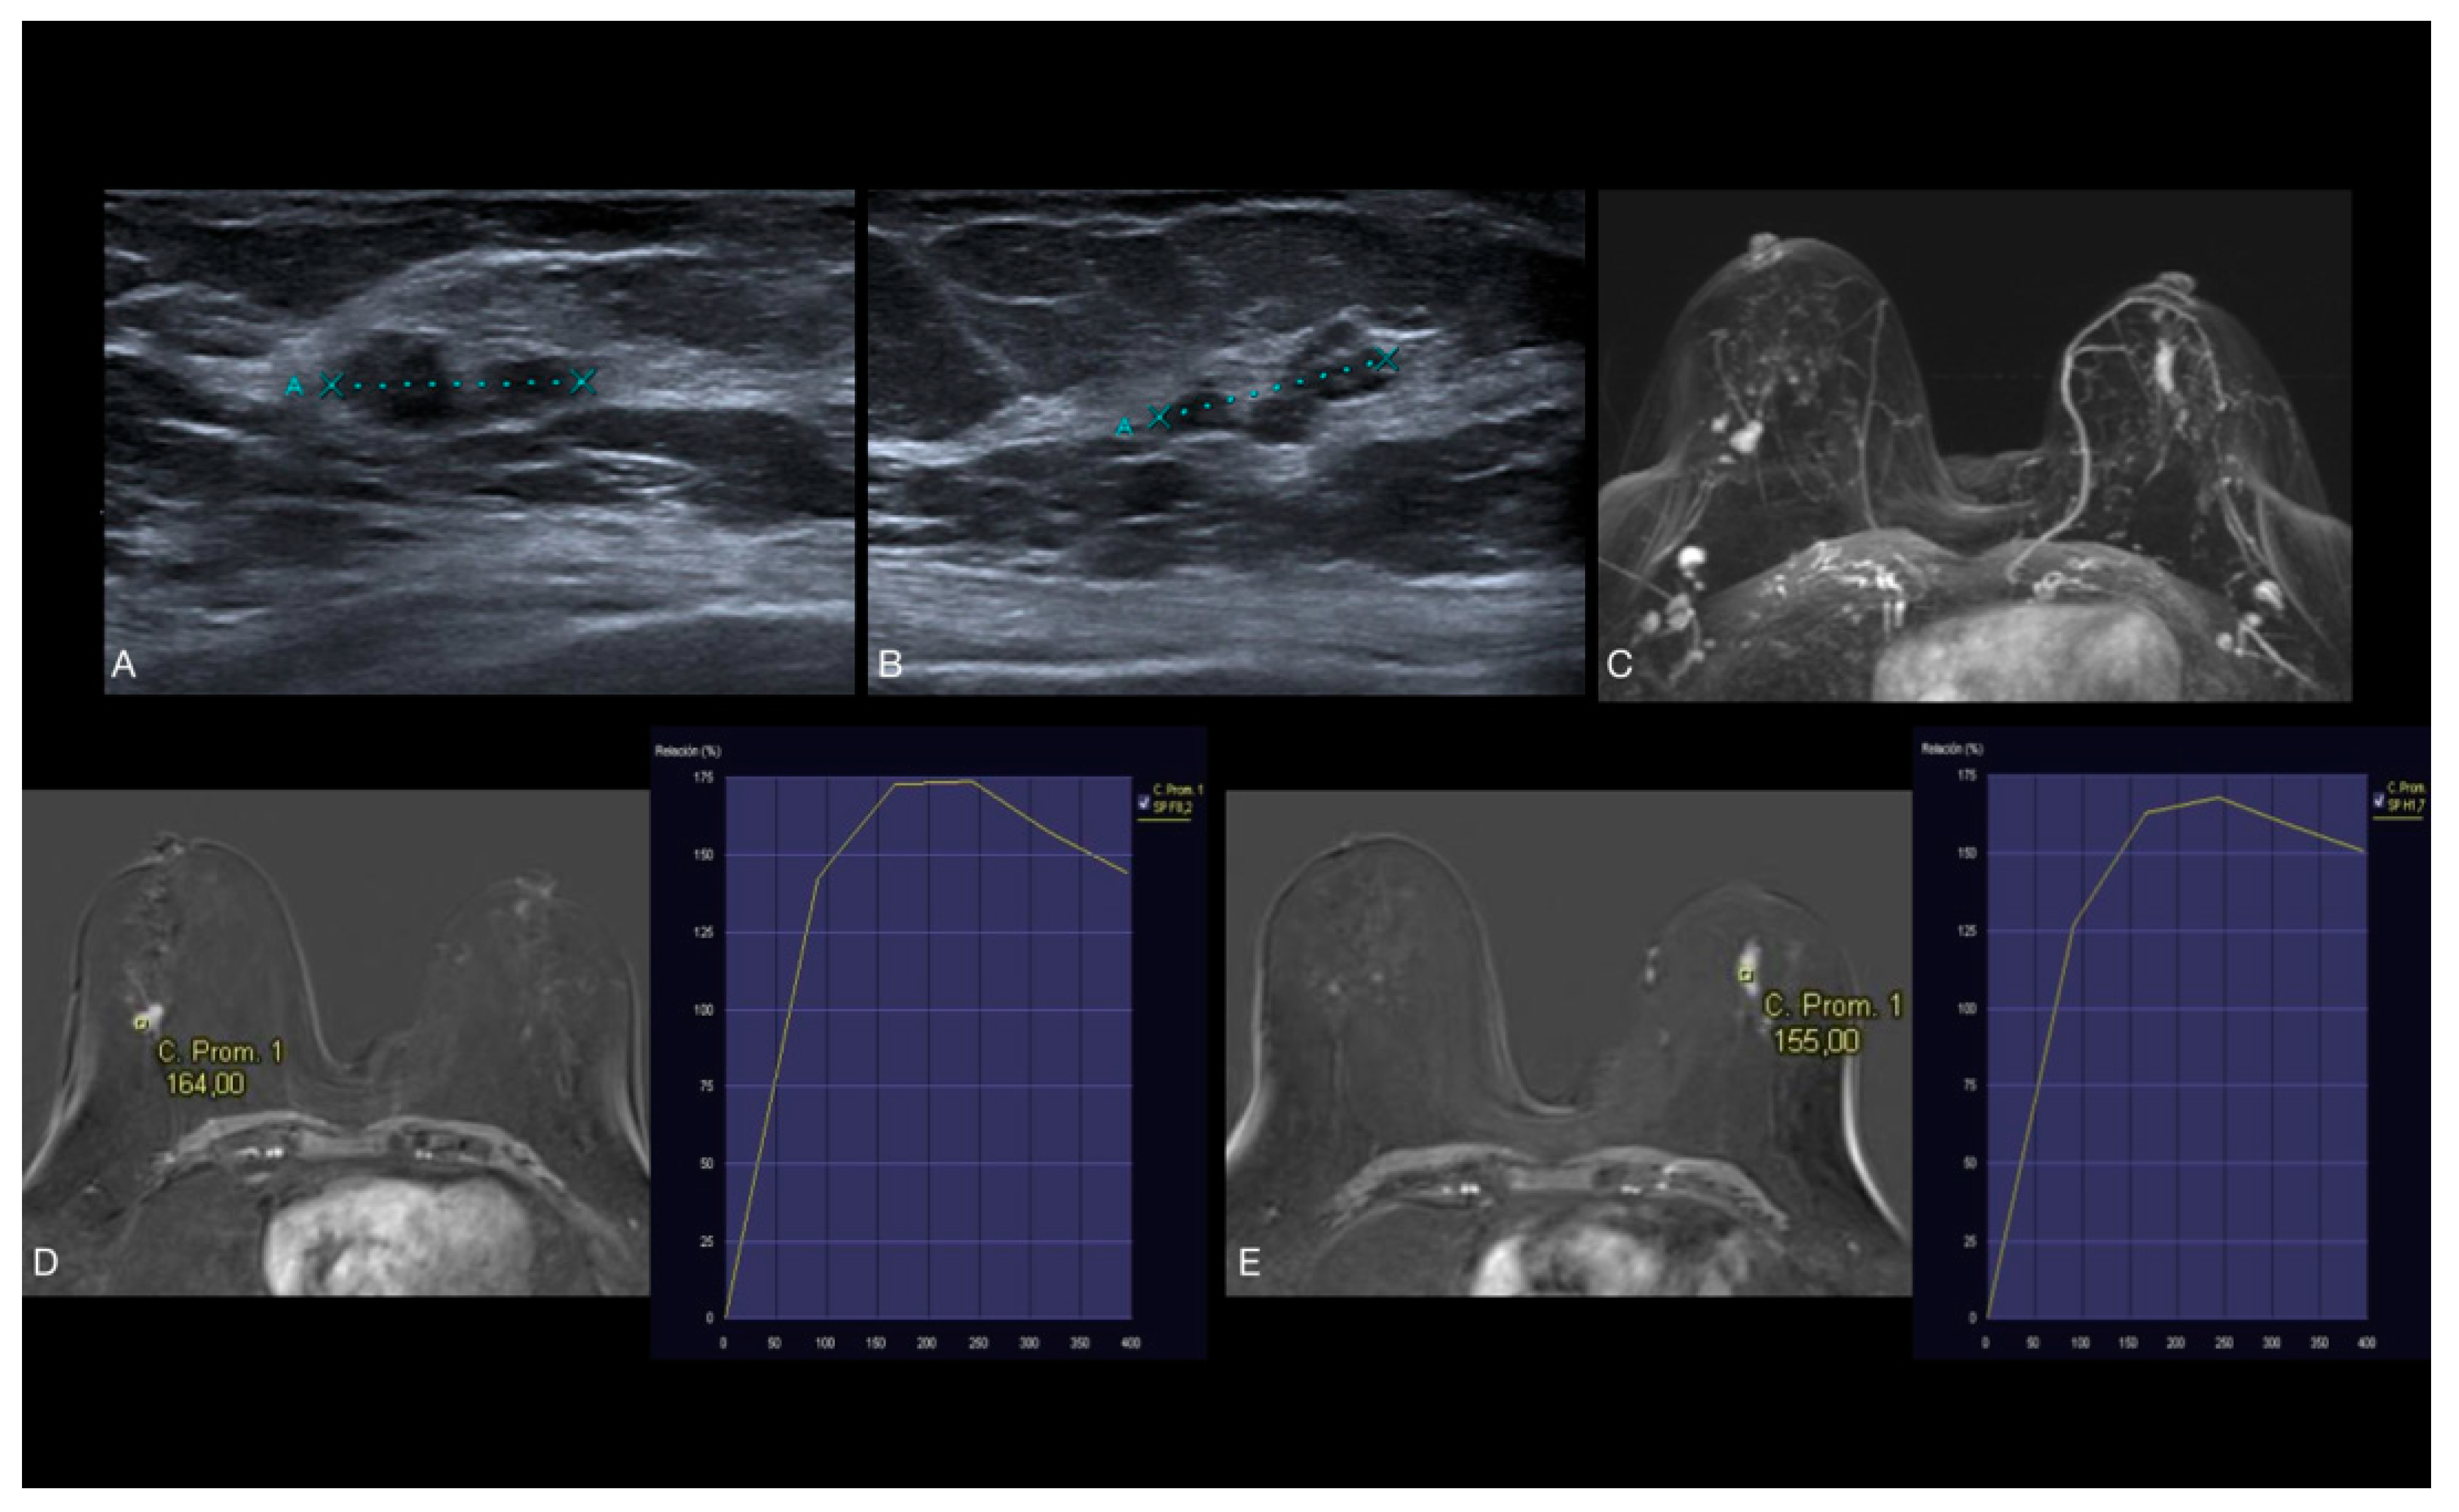

3.4. MRI Features

4.4. MRI Findings

| Curve type | ||||||||

| 1 | 3 (5.88%) | 3 (4.69%) | 0 (0%) | 6 (4.35%) | 0.49 1 | 1 | ||

| 2 | 43 (84.31%) | 57 (89.06%) | 19 (82.61%) | 119 (86.23%) | 0.34 | 0.64 | ||

| 3 | 5 (9.80%) | 4 (6.25%) | 4 (17.39%) | 13 (9.42%) | ||||